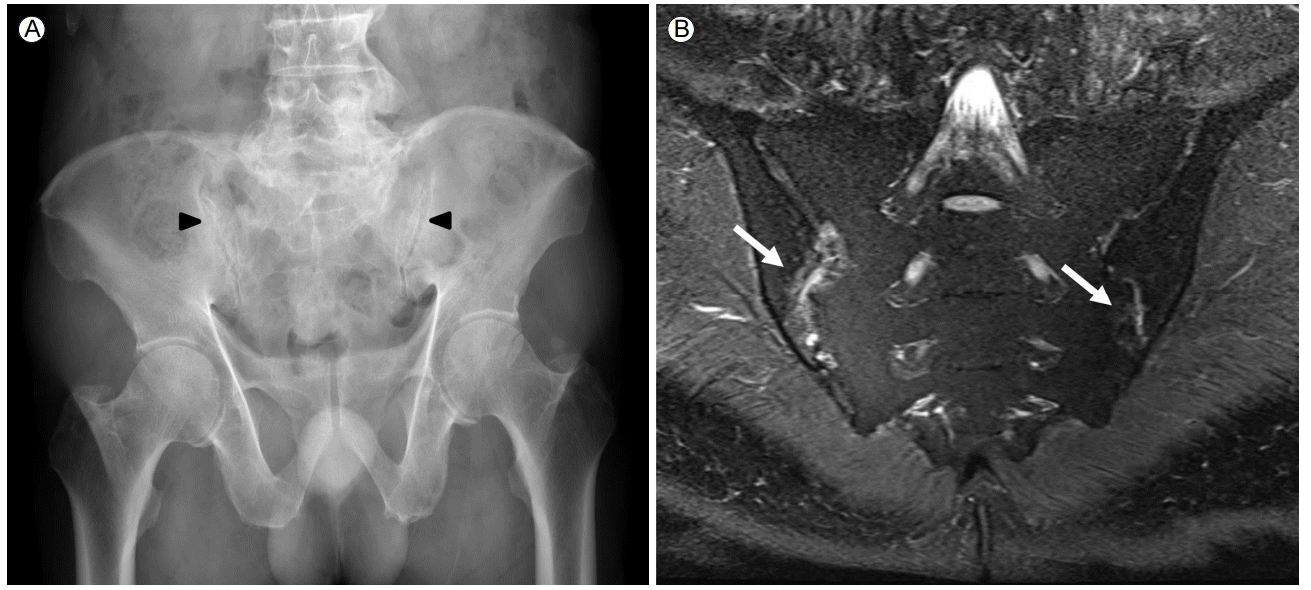

A 71-year-old male with AS was admitted to the hospital with abdominal distension and fever, which had persisted for one week. He was initially diagnosed with AS in March 2013, following complaints of left ankle pain with swelling along with inflammatory back pain. At the time of diagnosis, a pelvic plain X-ray (Fig. 1A) and magnetic resonance imaging (Fig. 1B) revealed active sacroiliitis. Erythrocyte sedimentation rate (ESR) was 120 mm/h (normal, 0-15 mm/h) and C-reactive protein (CRP) was 10.71 mg/dL (normal, 0.01-0.47 mg/dL); HLA-B27 was positive. He was initially treated with celecoxib, sulfasalazine, and methotrexate for three months. Because the treatment response was incomplete, infliximab treatment was began in June 2013. Screening for tuberculosis was performed before initiation of infliximab therapy, using a combination of chest x-ray, tuberculin skin test (TST), and interferon-γ release assay (IGRA). The chest x-ray was normal, and the TST and IGRA were negative. Consequently, infliximab therapy was started without tuberculosis prophylaxis. Infliximab (300 mg) was administered intravenously 11 times bi-monthly over the next 18 months. Infliximab therapy was effective, and the AS disease activity had diminished significantly prior to the most recent admission.

Sacroiliitis at the initial presentation. (A) Subchondral sclerosis and periarticular erosions can be seen in both sacroiliac joints (arrowheads, sacroiliitis, New York classification II). (B) T2-weighted fat-suppression pelvis magnetic resonance imaging revealed bone marrow edema and subchondral erosions (arrows).